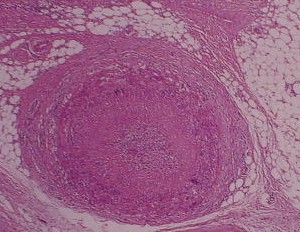

What does the above specimen show? Answer A cross-section of the artery which shows occlusion of the lumen and thickening of the intima and media. This is seen in giant cell arteritis. How does this condition normally affect the eye? a Answer Anterior ischaemic optic neuropathy by produing granulomatous mural inflammation of the posterior ciliary artery.